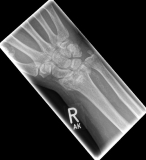

Handgelenk 1Often the inspection of the wrist already shows a suspected diagnosis. The accident mechanism must be clarified and after the physical examination, X-ray images of the wrist must be made in 2 levels.

In the classification of the distal radius fractures, the position of the fracture as well as a possible involvement of the articular surface are considered. Furthermore, the accident mechanism allows a classification of the fractures: the fall on the outstretched hand leads to a so-called extension fracture (Colles fracture), while the fall on the bent hand leads to a flexion fracture (Smith fracture).

Handgelenk 2The most common classification according to the Association for Osteosynthesis in fractures without involvement of the articular surface (A-fracture), fractures with partial joint involvement (B-fractures) and fractures with complete joint involvement (C-fracture). This results in indications for the therapeutic procedure.